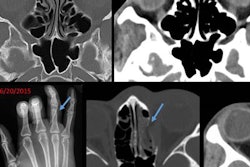

Fractures with high specificity for child abuse are classic metaphyseal corner fractures, multiple rib fractures (especially posterior), and sternal, clavicular, and spinous process fractures, Imsande and colleagues wrote. Fractures with moderate specificity are multiple fractures, including fractures in various stages of healing, epiphyseal separations, vertebral body fractures and separations, digital fractures, and complex skull fractures. Osseous injuries with low specificity for abuse include subperiosteal new bone formation, clavicular fractures, long-bone shaft fractures, and linear skull fractures.

"Normal structures and variants can mimic injuries sustained from abuse, and the radiologist must be aware of the imaging appearances of normally developing bones," they noted. "For example, Wormian bones and cranial sutures can be mistaken for abusive injury, as can ossification centers, vertebral body wedging, pseudosubluxation, and nutrient canals within the spine. Within the appendicular skeleton, physiologic periosteal reaction, metaphyseal step-off, metaphyseal beak, metaphyseal spur, metaphyseal fragmentation, distal ulna metaphyseal cupping, proximal tibial cortical irregularity, and nutrient vessels can mimic abuse."